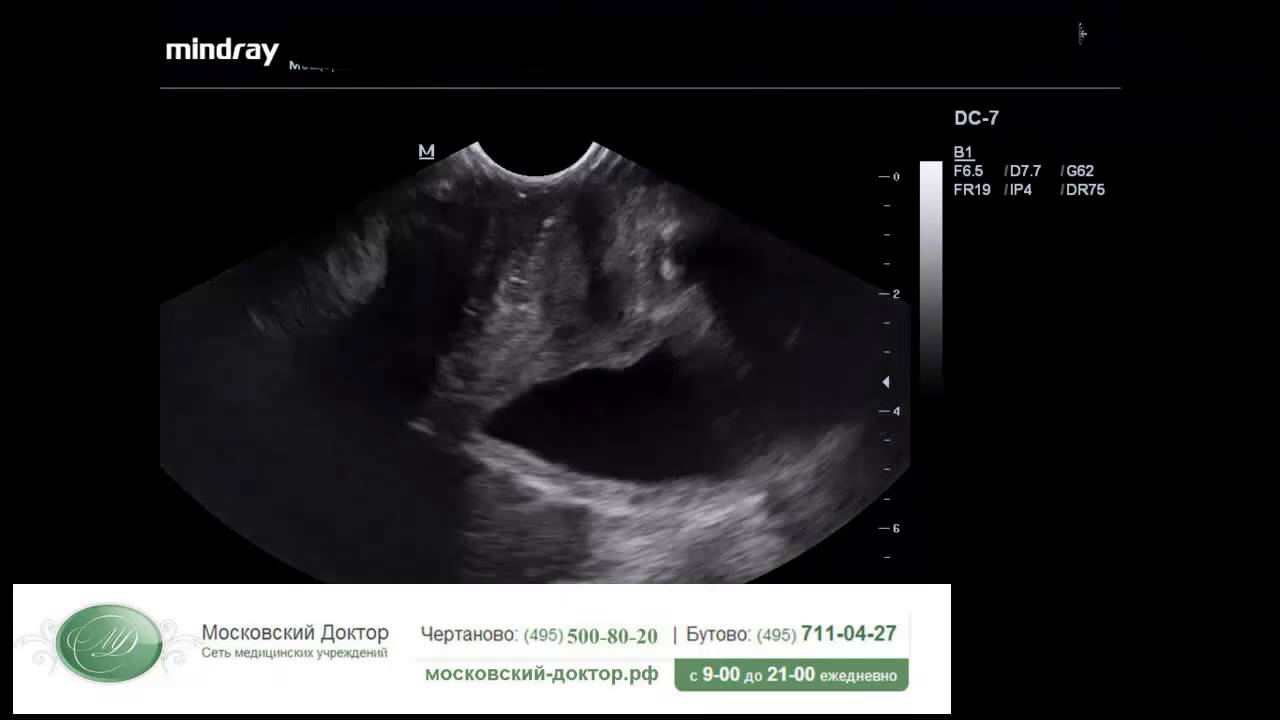

Этот метод диагностики безопасен и безболезнен. Во время ультразвукового исследования датчик отправляет сигналы, проходящие через ткани органа и отражающиеся от них с разной интенсивностью. Отраженные волны обрабатываются устройством и выводятся на экран аппарата.

Специалист анализирует характеристики органа, выявляя заболевания паращитовидной железы и патологии околощитовидных лимфатических узлов. УЗИ также позволяет оценить степень тяжести заболевания и результаты лечения.